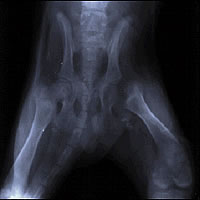

a) Displasia de Cadera